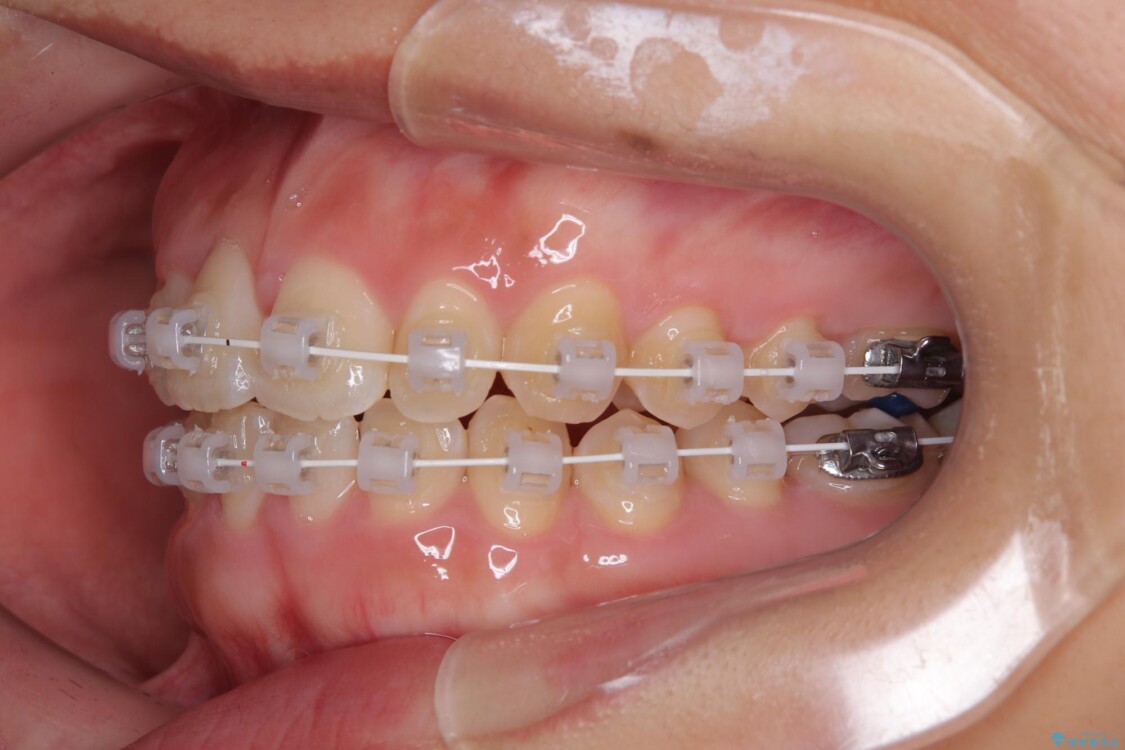

治療途中

• 目立ちにくい表側装置で1年完了!狭いアーチを側方拡大し前歯のデコボコを整えた症例 治療途中画像

・アーチを側方に拡大して歯が並ぶスペースを確保

・目立ちにくい審美装置による矯正